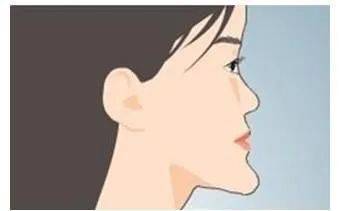

地包天儿童与正常儿童最明显的差别就是前者的面中部平坦或凹陷,下颌前突,主要是由于上颌骨的发育受到了下颌骨的限制引起的。

如何预防地包天?

1、帮助孩子纠正不良的口腔习惯。

2、鼓励母乳喂养。只能人工喂养的儿童吃奶的姿势应为侧卧,不要养成仰面吃奶的习惯。

3、尽早去专业口腔科做检查,一旦发现问题就需要进行早期矫治。

4、在幼儿时期接受矫正,只需要简单的戴矫正器;如果到成年只能进行手术来矫正了。